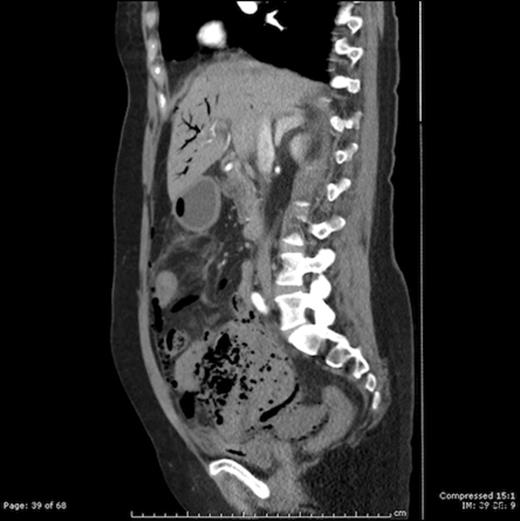

A 66 years old female presented with acute lower abdominal pain for 2 days. She had a background of hypertension and mesenteric angina. General examination revealed tachycardia and pallor. On abdominal examination, there was tenderness and rigidity in the lower abdomen with signs of peritonitis. Blood results included a CRP of 242, WCC 9.3, mildly elevated urea and creatinine levels, bilirubin 86 and evidence of metabolic acidosis and lactate of 4.2. CT scan revealed intestinal pneumatosis affecting the ileal loops, with free gas in the abdominal cavity and gas in the portal venous system, in keeping with acute ischemia and perforation involving ileal bowel loops (Figure 1 and 2)

CT scan showing portal venous gas and pneumatosis intestinalis in a large intraabdominal cystic mass (Gangrenous Meckel’s Diverticulum)